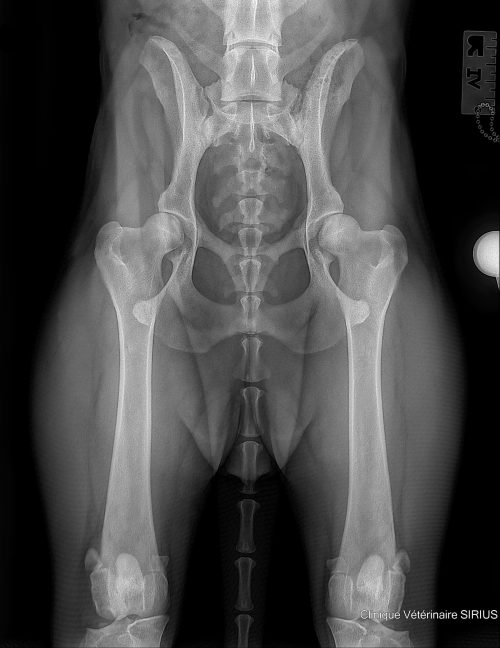

Exemple de dépistage officiel FCI sur un Beauceron après 12 mois révolus. Ce chien a été classé en “A”.

La radiographie ventro-dorsale en extension des membres postérieurs est un examen standardisé, largement utilisé pour le dépistage officiel dans plusieurs systèmes de cotation. Elle évalue la congruence, la profondeur acétabulaire, la forme de la tête fémorale, l’alignement, et surtout les signes d’arthrose lorsque celle-ci est déjà installée. Elle reste indispensable pour décrire l’état morphologique global et pour suivre l’évolution.

Cependant, elle ne met pas toujours en évidence l’instabilité initiale, car l’extension et la rotation interne peuvent, chez certains chiens, réduire artificiellement la subluxation. Chez le jeune chien, l’absence d’arthrose est la règle, et l’examen morphologique peut être peu discriminant pour prédire le futur. En pratique, cela signifie que la radiographie en extension doit être considérée comme une pièce du puzzle, mais rarement comme la seule réponse quand l’objectif est de prédire l’évolution dès les premiers mois de vie.